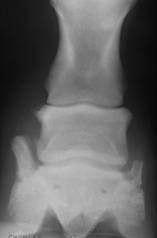

Čiurnos sąnario rentgenogramose tiek dešinėje, tiek kairėje pusėje OCD pasireiškė tokiu pat dažnumu – po aštuonis atvejus. Osteochondrinių atplaišų dydis sąnariuose svyravo nuo žirnio iki pupos dydžio.

Dažniausiai pažeidimai buvo lokalizuoti dorsaliai čiurnos sąnario, plantariniame paviršiuje, rečiau – palmariniame paviršiuje. Dviem atvejais buvo nustatyti įtrūkimai sąnario sagitalinėje kameroje.

Taip pat dviems arkliams buvo diagnozuotas abiejų čiurnos sąnarių, panašaus sunkumo laipsnio OCD.

![]()

25 pav. Kairėje – sveikas čiurnos sąnarys, dešinėje – sąnarys, pažeistas OCD.